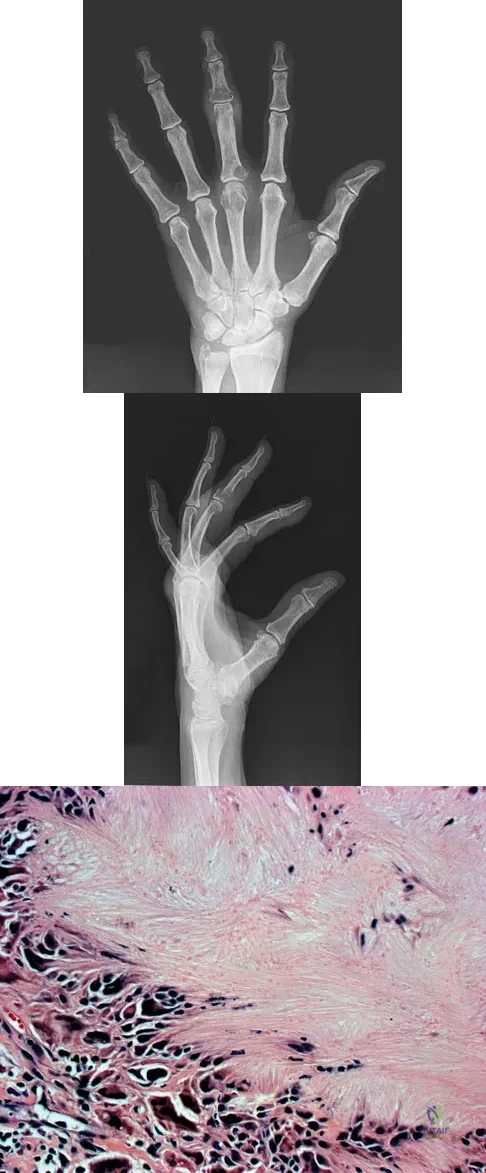

An 83-year-old woman reports pain in her left middle finger after a minor injury. Laboratory studies show a WBC count of 7,000/mm3, an erythrocyte sedimentation rate of 3 mm/h, a uric acid of 10.4 mg/dL, and a normal serum protein electrophoresis. Radiographs are shown in Figures 49a and 49b. A core biopsy specimen is shown is Figure 49c. In addition to treatment of the finger fracture, treatment should include

This clinical picture is most consistent with periarticular erosions from gout. The patient has multiple periarticular lytic lesions in the hand. The laboratory studies show an elevated serum uric acid level, and the biopsy specimen demonstrates acute and chronic inflammation with prominent clefts. Therefore, the preferred treatment is systemic control of her gout. Radiation therapy, chemotherapy, and/or amputation should be considered for a malignancy; however, the pathology does not demonstrate any evidence of pleomorphism, high nuclear-to-cytoplasmic ratio, nuclear atypia, or mitotic activity. Antibiotics for an infectious process is a consideration, but the minimal elevation in the WBC count and erythrocyte sedimentation rate does not support an infectious process. Wise CM: Crystal-associated arthritis in the elderly. Clin Geriatr Med 2005;21:491-511.